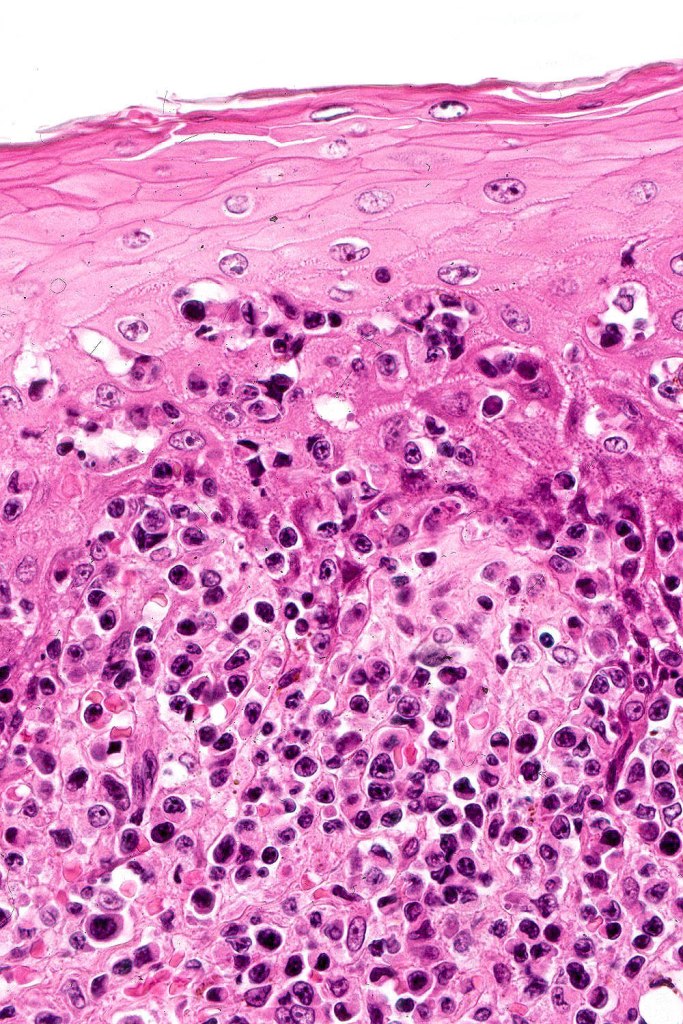

Histological features

The histological hallmark of mycosis fungoides is the presence of large atypical lymphocytes with a convoluted/cerebriform nuclear border (Sézary cells). These may be found at the epidermal-dermal jnuction and as collections within the epidermis (Pautrier microabscess). These are most easily found in plaque stage disease. The epidermal component can be subtle in patch stage disease and is often lost in tumor stage dsease. The classification into patch, plaque & tumor stage disease is less helpful histologically as the features merge from one to the other. It is all a matter of degree.

Tumor Stage Disease

•Epidermotropism is often minimal or absent

•Dense, broad diffuse or nodular, dermal infiltrate often extending into the subcutaneous fat

•Abundant Sézary cells. Frequently accompanied by very pleomorphic forms

•Mitoses often abundant, frequently abnormal

•CD30 expression correlates with transformation (cells X4 size of small lymphocytes comprising 25% or more of the infiltrate or the presence of a distinct large nodule)